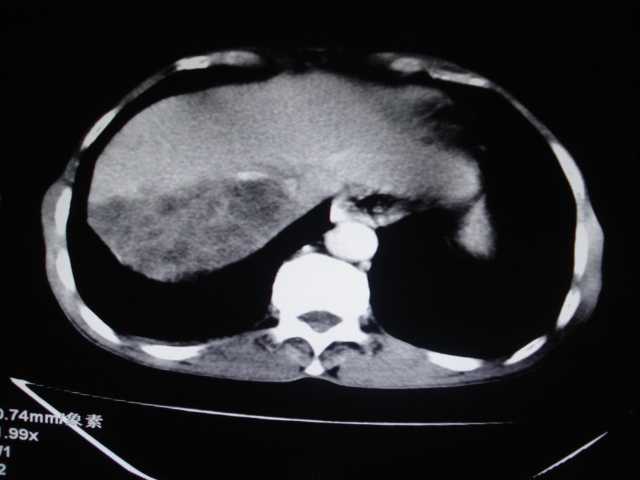

标题: CT24041:肝脏占位,请会诊!

男性,62岁。肝右叶占位,平扫及增强如下,延迟期为15分钟扫描。